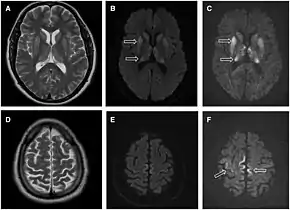

MRI of iCJD because of growth hormone

The defective protein can be transmitted by contaminated harvested human brain products, corneal grafts,[22] dural grafts,[23] or electrode[24] implants and human growth hormone.[25]

Brain MRI is the most useful imaging modality for changes related to CJD. Of the MRI sequences, diffuse-weighted imaging sequences are most sensitive. Characteristic findings are as follows:

dwMRI, FDG PET and post mortem histology from a patient who presented with sCJD aged 66

• Focal or diffuse diffusion-restriction involving the cerebral cortex and/or basal ganglia. In about 24% of cases DWI shows only cortical hyperintensity; in 68%, cortical and subcortical abnormalities; and in 5%, only subcortical anomalies.[44] The most iconic and striking cortical abnormality has been called "cortical ribboning" or "cortical ribbon sign" due to hyperintensities resembling ribbons appearing in the cortex on MRI.[45] The involvement of the thalamus can be found in sCJD, is even stronger and constant in vCJD.[46]

• Varying degree of symmetric T2 hyperintense signal changes in the basal ganglia (i.e., caudate and putamen), and to a lesser extent globus pallidus and occipital cortex.[42]

• Cerebellar atrophy

Brain FDG PET-CT tends to be markedly abnormal, and is increasingly used in the investigation of dementias.

• Patients with CJD will normally have hypometabolism on FDG PET.[47]